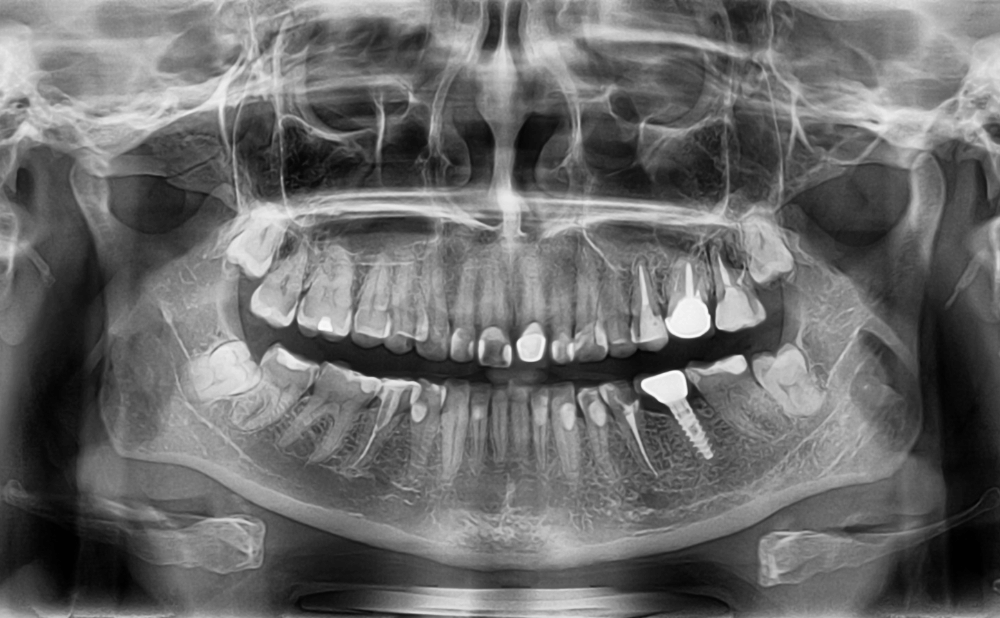

信頼できる歯科医院では、歯科用CTを使った3D画像診断で、顎の骨の厚みや神経の位置をミリ単位で正確に把握します。